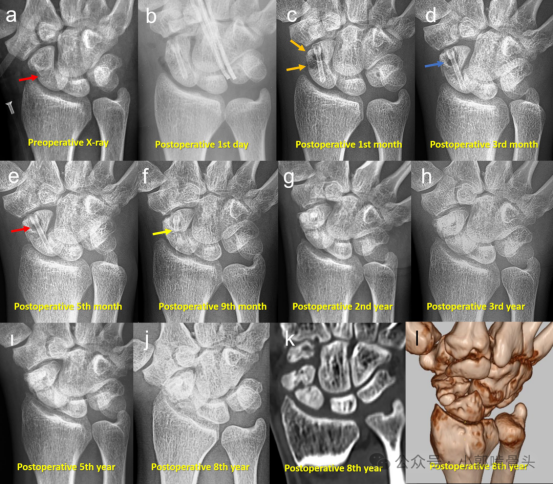

一名22岁男性患者因摩托车事故导致舟骨骨折(Herbert B2型,即舟骨腰部完全骨折),接受了镁螺钉内固定治疗,并进行了系列影像学随访。患者为非吸烟者,术后影像学表现如下:(a) 术前X线片显示急性舟骨骨折(红色箭头标记)。(b) 术后第1天X线片显示镁螺钉内固定的位置。(c) 术后1个月随访X线片显示骨内气体形成(橙色箭头标记)。(d) 术后3个月随访X线片显示气体形成减少(蓝色箭头标记)。(e) 术后5个月随访X线片显示骨内仍有气体,尤其是螺钉头部周围(红色箭头标记)(f) 术后9个月随访X线片显示螺钉断裂及骨不连征象(黄色箭头标记)。(g) 术后2年、(h) 3年和(i) 5年随访X线片显示明确的骨不连及螺钉轮廓逐渐模糊。(j) 术后8年最终随访X线片显示舟骨不愈合进展性塌陷(SNAC)及舟骨碎裂。(k) CT扫描和(l) 3D CT重建在术后8年随访中也证实了上述影像学表现。